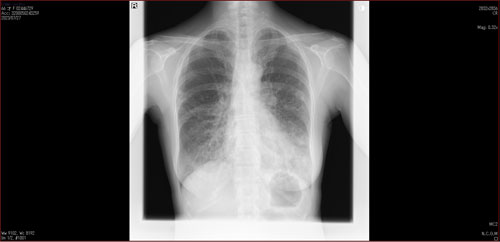

肺X線画像

- 2023.07.27 肺炎と診断された画像(国立系病院)